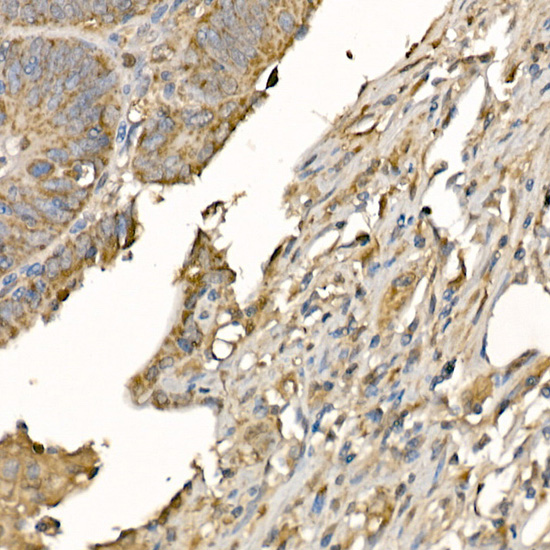

Immunohistochemistry of paraffin-embedded human colon carcinoma using GSDMD (Full Length+N terminal) Rabbit pAb.